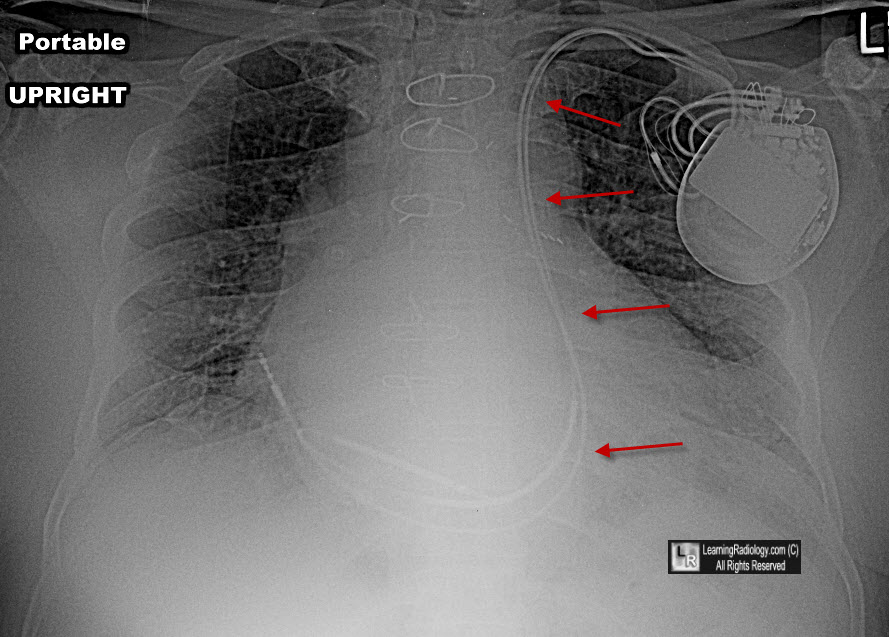

Persistent Left Superior Vena Cava

- Incidence-uncommon

- 0.3% of general population;

- 4.3-11% of patients with CHD

- Two types

- Persistent left SVC connecting to right atrium

via coronary sinus is only common anomaly of SVC (90% of this

anomaly)

- In other 10%, persistent SVC connects to left

atrium

- Most with connection to left atrium have

associated ASD or heterotaxy syndromes

- This produces a right-to-left shunt of a

rather small magnitude

- Course of persistent left SVC

- Draining into right atrium

- Starts at junction of left subclavian vein

and left internal jugular

- Passes lateral to aortic arch

- Receives left superior intercostal vein

- Anterior to left hilum

- Joined by hemiazygos system

- Crosses posterior wall of left atrium

- Receives great cardiac vein to become

coronary sinus (common)

Yellow arrows point to left-sided persistent SVC

passing lateral to aortic arch and anterior to left hilum

The leads of the AICD enter the left subclavian vein and subsequently drain into a persistent left superior vena cava (red arrows) and from there into right atrium and right ventricle.